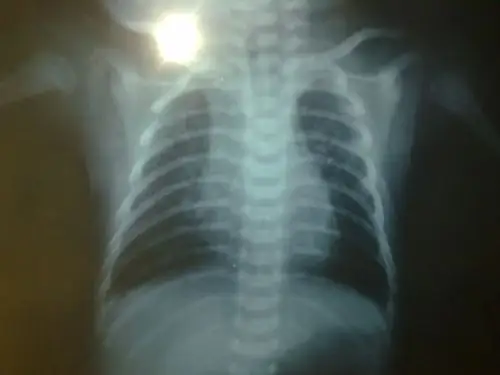

小儿肺炎好治吗

其它 秋冬季节小儿支气管炎了解 写美篇 什么是支气管肺炎呢?